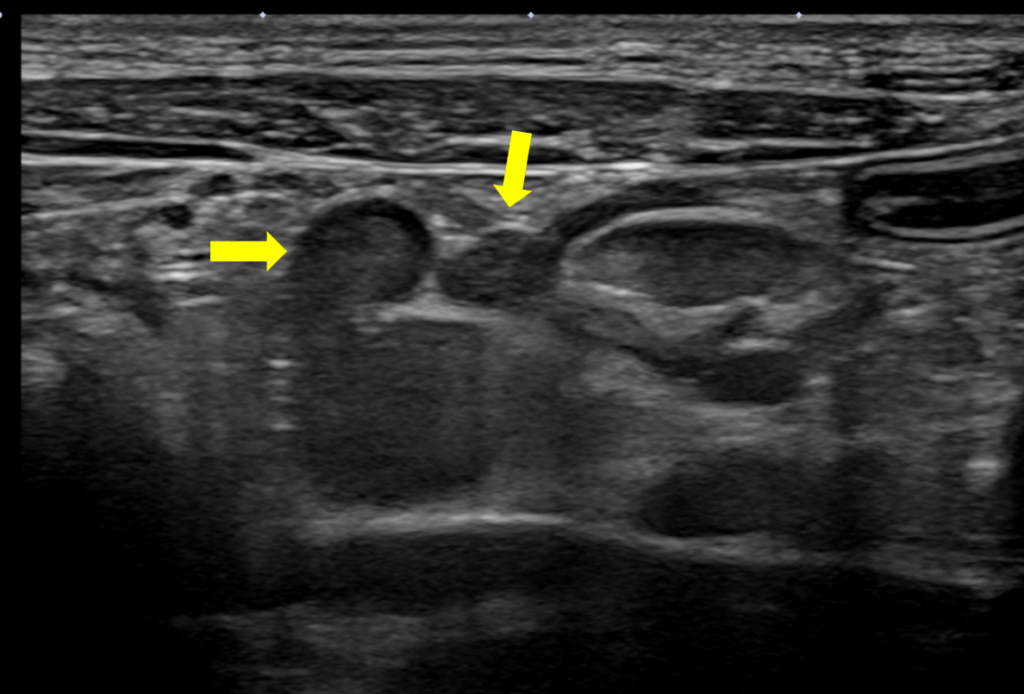

↑リンパ節の腫れ

本来リンパ節はほとんどエコーで映りませんが、リンパ節が腫れていると黄色矢印のようにエコーではっきりと映ります。